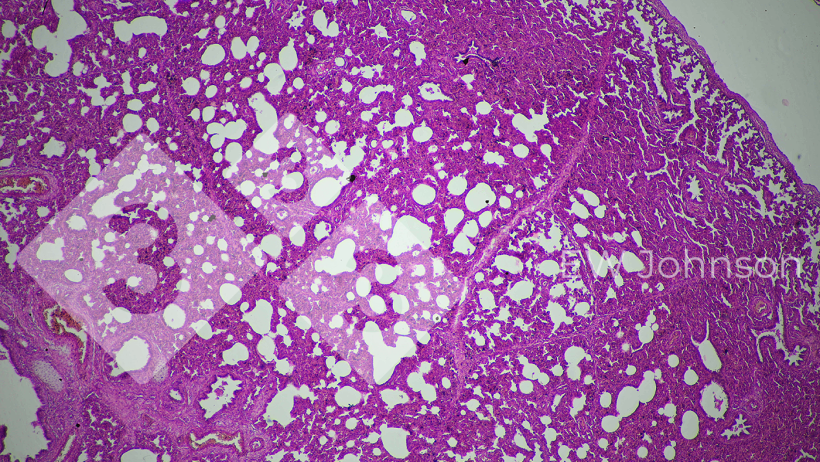

La PCR è risultata negativa per PRRS, pseudorabbia (PRV, Malattia di Aujeszky), circovirus suini PCV2 e PCV3, peste suina classica (PSC) e peste suina africana (PSA). L'allevamento era noto per essere indenne da PRRS, PRV, PSC e PSA prima di questo evento. La PCR per il Getahvirus nel polmone dei suinetti è risultata altamente positiva. L'istopatologia ha rivelato una grave polmonite interstiziale (Figura 3) e meningoencefalite fibrinoemorragica (Figura 4). È stata diagnosticata la malattia perinatale da Getahvirus. L'azienda è stata informata che questa malattia è trasmessa principalmente dalle zanzare e sono state applicate misure di controllo. Non ci sono stati ulteriori casi o segni clinici nell'allevamento e la produzione è tornata alla normalità.

Figura 3. La polmonite interstiziale suggerisce una possibile origine virale.